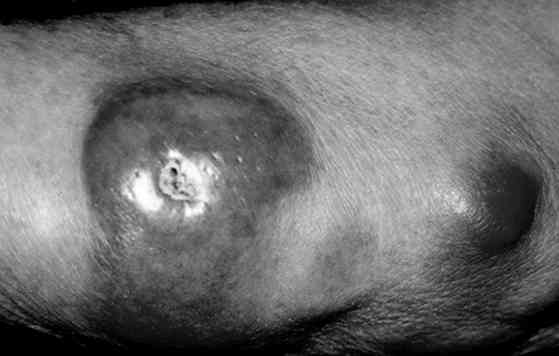

B-Cell Lymphoma of the Skin

these can present as a nodule (as above) or large nodules (go here) or flat patches or plaques (go here)

In contrast to CTCL, which progresses slowly from a patch to a plaque to a tumor, PCBCL usually presents as a solitary, circumscribed reddish to violaceous papule, plaque, or nodule.Occasionally, it present as multiple or grouped lesions in a localized skin region. Surrounding erythema, smaller papules, infiltrative plaques, and/or figurate erythematous patches have been reported. Overlying scale or ulceration is rare. Specific subtypes may have a predilection for particular areas of the body, such as the trunk and scalp for follicular center cell (FCC) lymphomas and the extremities for immunocytomas. The main clinical differential diagnosis is reactive lymphoid hyperplasia, which has similar features.